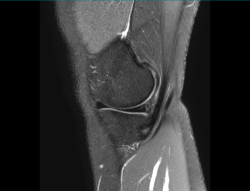

1.2.3. Ligamento cruzado posterior (LCP) (Figuras 45 y 46)

Figura 45. Corte de secuencia sagital T2 Fat-Sat de resonancia magnética: ligamento cruzado posterior normal.

Figura 46. Corte de secuencia sagital T2 Fat-Sat de resonancia magnética: rotura de ligamento cruzado posterior distal.